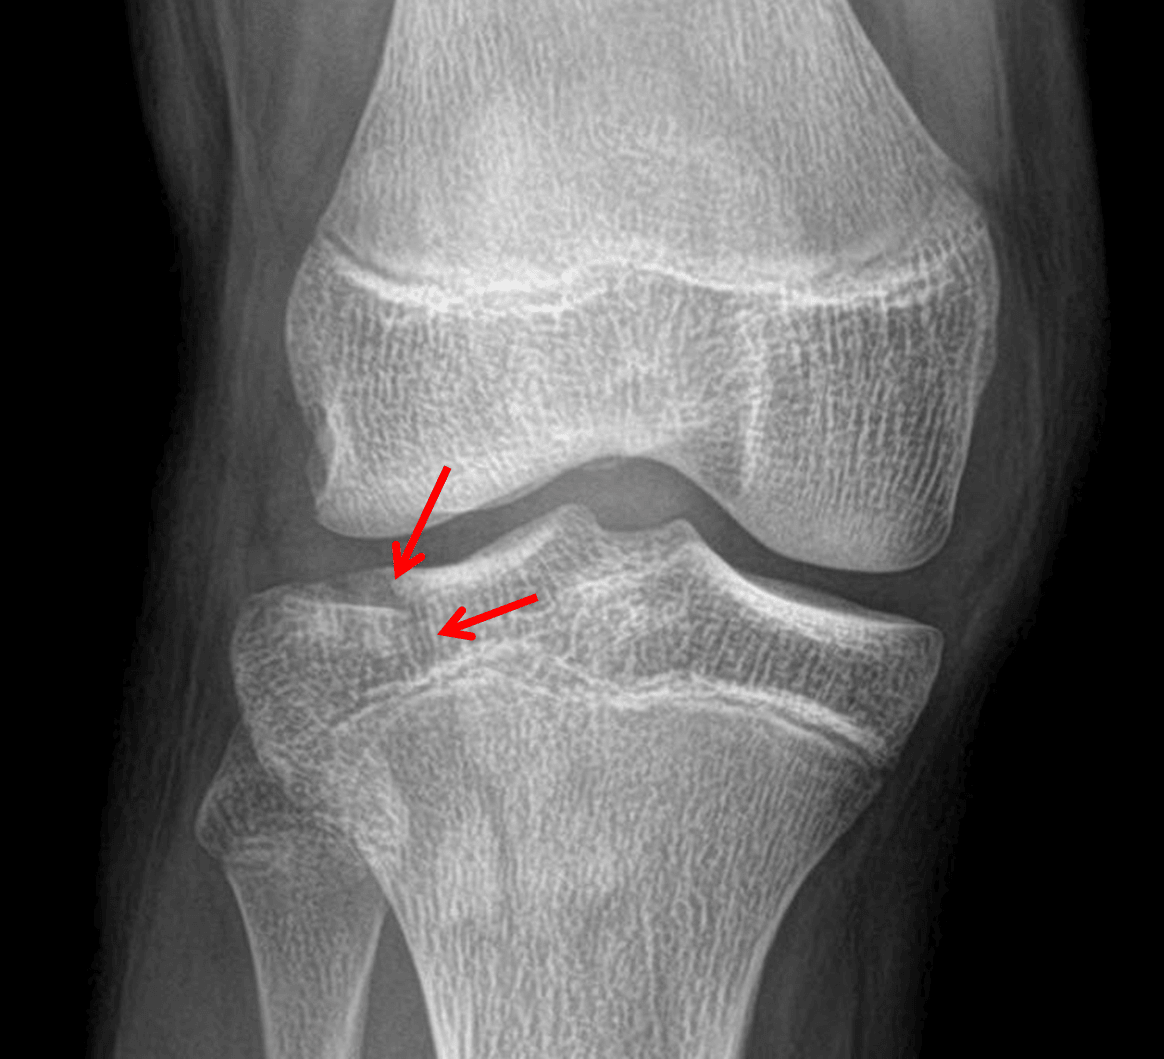

Red arrows: minimally depressed Saltar IV fracture of the lateral tibial plateau (Schatzker I).

Acute minimally depressed Salter IV fracture of the lateral tibial plateau. No physeal widening.

Large joint effusion.

No joint malalignment.